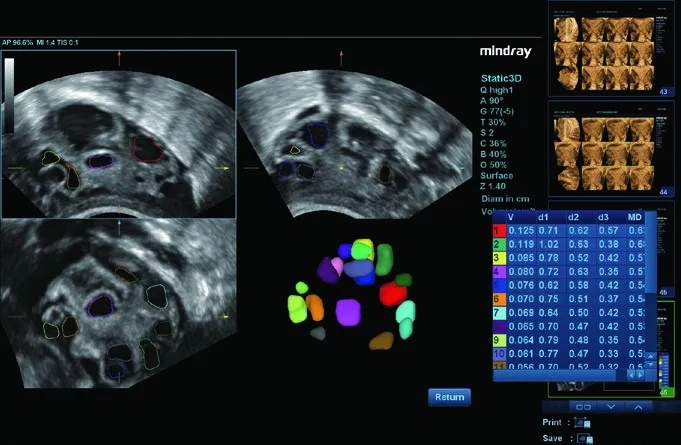

• Smart 3D — ПО для построения 3D-изображений с использованием 2D-датчиков;